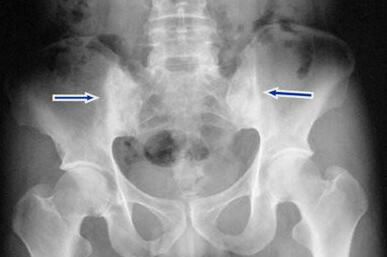

检查结果:ESR增快,为60mm/h,C反应蛋白(CRP)50.5mg/l, HLA-B27(人体抗原白细胞)阴性(-);骶髂关节,椎间小关节和髋关节间隙消失,出现骨性强直;脊柱韧带钙化,形成竹节状外观,骨质疏松严重。

(图:X线片显示其脊柱韧带钙化,骶髂关节强直)